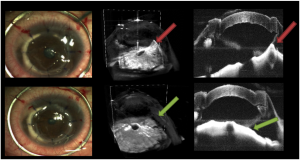

The fourth finalist group is Joseph Izatt and his team at Duke University for their work in using GPU-accelerated, real-time stereoscopic 3D data for eye surgery. A single Titan GPU takes a stream of raw “optical coherence tomography” (OCT) data, processes it, and renders 3D volumetric images.

Comparison of conventional rendering (left) and enhanced ray casting with denoising (right) of the anterior segment

These images, at a resolution of a few micrometers, are projected into microscope eyepieces. With Nvidia 3D Vision-ready monitors and 3D glasses, live stereoscopic data can be viewed by both a surgeon using the microscope and a group observing the operation as it occurs. The blog post is titled “How GPUs Help Eye Surgeons See 20/20 in the Operating Room.”